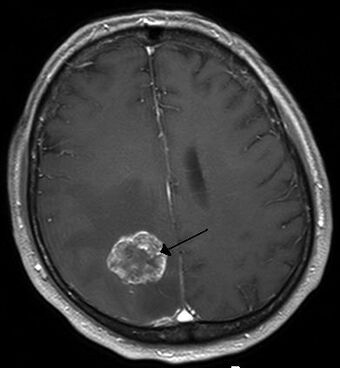

Hirnmetastase MRT-T1 KM.jpg

Brain metastasis in the right cerebral hemisphere from lung cancer, shown on magnetic resonance imaging